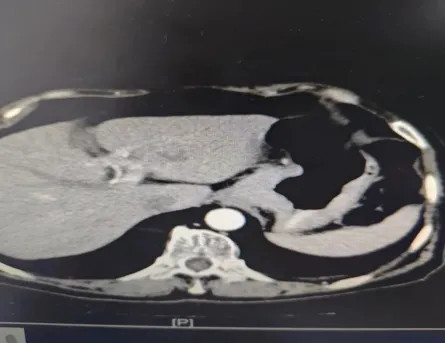

术后经胃肠外科护士团队精心护理,指导患者术后康复工作,患者恢复良好,术后第5天,消化道造影显示吻合口愈合良好,可以开始正常进食,一周左右患者成功出院。

胃肠消化道造影